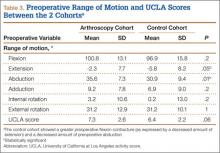

A comparison of the results of the 1:2 matching analysis between the arthroscopy and control cohorts is presented in Table 2. There was no significant difference in the preoperative age, BMI, femoral head size, HHS, or WOMAC score between the 2 cohorts. However, the control cohort did show a more severe, preoperative flexion contracture (as expressed by a decreased amount of extension) and a decreased amount of preoperative abduction (Table 3). The preoperative UCLA activity score was also decreased in the control cohort, but this was not statistically significant.